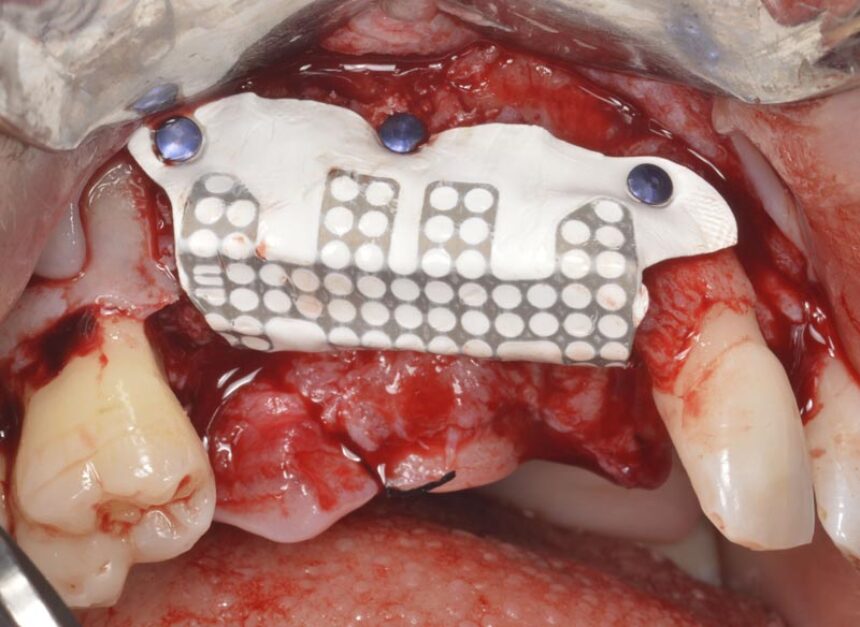

More specifically, ο Dr. Massimo Simion is one of the pioneers of the Guided Bone Regeneration procedure in the area of implant dentistry. Through his thirty-year experience, he will convey his experiences in this area, as well as the secrets of success in cases of extended deficit of the alveolar crest, in both the maxilla and the mandible, and he is going to present the management of various complications that may arise in handling such cases, which is a challenge for clinicians.

Horizontal and Vertical Ridge Augmentation: scientific background - surgical techniques – resorbable and non-resorbable membranes - bone graft harvesting from intra-oral sites – video

Management of GBR complications.